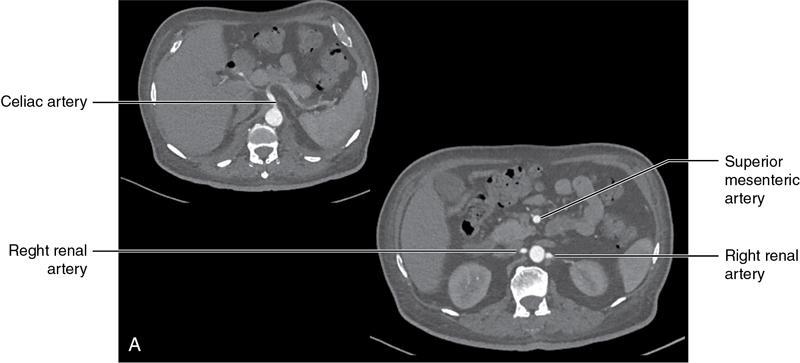

CROSS SECTIONAL ANATOMY OF ABDOMEN Satya Jha NORMAL ANATOMY OF ABDOMEN AND PELVIS Amandeep Singh The two major surfaces: The anterior and posterior layers of the coronary ligament converge on bare area (not covered by peritoneum). Its right and left margins form the right and left triangular ligaments. The right triangular ligament extends toward the diaphragm and separates right subphrenic space from right subhepatic space. The left triangular ligament gives tracts extending to the diaphragm and falciform ligament and does not compartmentalize the left subphrenic space. Ligamentum teres or the obliterated umblical vein is contained in falciform ligament which attaches the liver to anterior abdominal wall. The main portal vein, the proper hepatic artery and the common bile duct are contained within investing peritoneal folds of hepatoduodenal ligament at the porta hepatis (Fig. 7.2.2.1). Liver is divided into eight segments which are functionally independent and have their own vascular supply and biliary drainage. Arterial circulation: The branches of the hepatic artery accompanying the portal veins. Hepatic venous system: The right, middle, and left hepatic veins draining into IVC (Figs. 7.2.2.2 and 7.2.2.3). The gallbladder is a blind pear-shaped muscular membranous sac which is an embryologic derivative of the foregut, is a pouch lying along the undersurface of the liver. The gallbladder fossa is located in the plane of the interlobar fissure, which lies between the right and left hepatic lobes. Its major function is to store and concentrate bile which is produced by the liver. It measures approximately 4 cm in diameter when it is normally distended. Gallbladder is a smaller tubular structure in contracted state. The normal gallbladder wall thickness ranges from 1 to 3 mm. The gallbladder is divided into the fundus, body and neck. Infundibulum is present in the region of neck of the gallbladder, which is called the Hartmann pouch, where gallstones are usually impacted. Intrahepatic biliary radicles (IHBRs) scattered throughout the liver get confluent towards the hilum. They unite to form the right and left main hepatic ducts which further unite to form common hepatic duct (CHD) at the hilum. Common bile duct is formed by the union of cystic duct with common hepatic duct. The main pancreatic duct is joined with the common bile duct to form the ampulla of Vater at the major duodenal papilla (Figs. 7.2.2.4 and 7.2.2.5). Pancreas is located in anterior pararenal space of retroperitoneum anterior to perirenal (Gerota’s) fascia and posterior to parietal peritoneum. It is divided into head, uncinate process, neck, body and tail from right to left. Pancreas lies anterior to portal vein, which marks the point of transition between the body and neck. The region between head of pancreas and second and third parts of duodenum is known as the pancreatic groove. In postnephrectomy cases or with agenesis of kidney or ectopic kidney, pancreas moves posteriorly to partially fill in the empty renal fossa; its soft tissue density should not be mistaken for recurrent tumour. It is located in the pancreatic groove and is bounded superiorly by the duodenal bulb, laterally by second portion of duodenum, inferiorly by third portion of duodenum, medially by superior mesenteric vein and anterior to inferior vena cava. It is a wedge or wedge shaped lying posterior to superior mesenteric artery and vein. It is an imaginary junction between the head and body and lies directly over the junction of the splenic vein and superior mesenteric vein. It is located posterior to the lesser sac and anterior to the aorta, left adrenal gland, left kidney, and renal vessels and runs obliquely upward to the left of the superior mesenteric vessels. It is situated median to the colonic flexure and anterior to the left kidney. It is located in close proximity to the splenic hilum without a notable relation with the body of pancreas. It is seen anterior to the left kidney and median to the colonic flexure. The distal part of the tail passes between the peritoneal layers of the splenorenal ligament (Fig. 7.2.2.6 and 7.2.2.7).